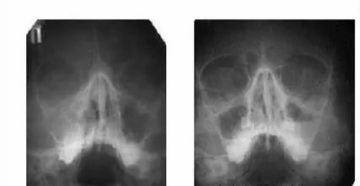

Причины субтотального затемнения гайморовых пазух на рентгенологическом снимке Рентген пазух носа назначается врачами при подозрении…